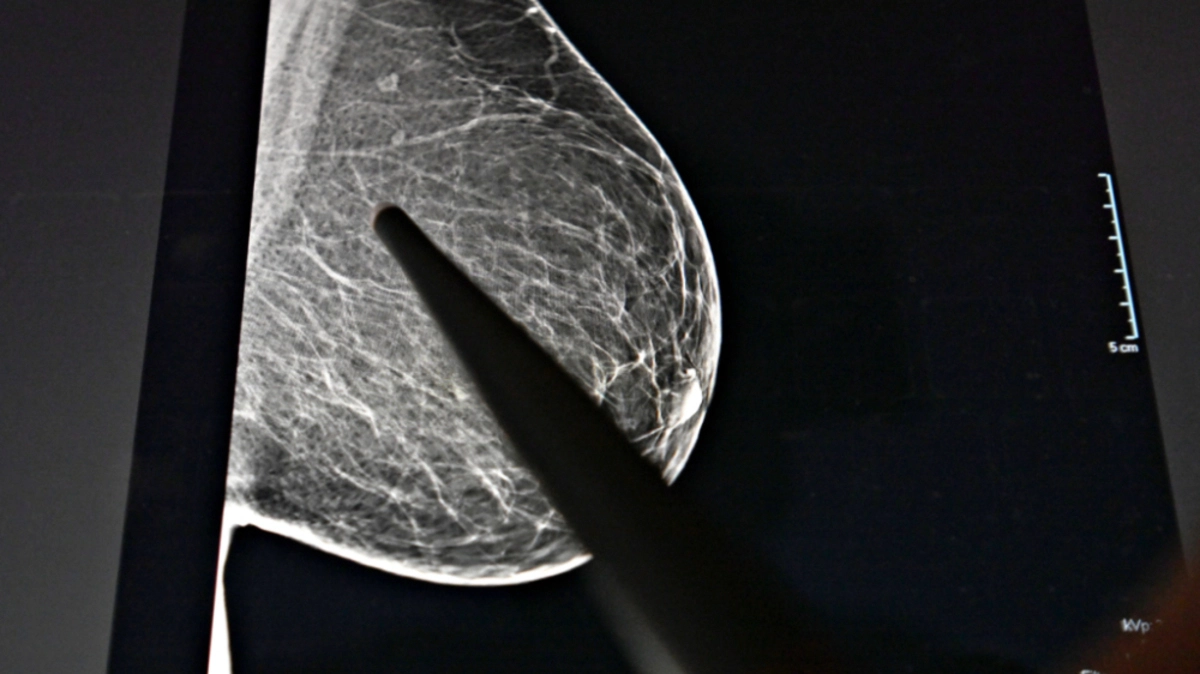

Häufigste Diagnose bei Frauen war Brustkrebs | Häufigste Diagnose bei Frauen war Brustkrebs

Häufigste Diagnose bei Frauen war Brustkrebs